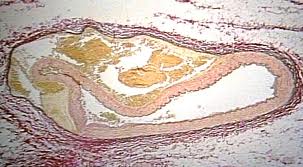

A dissection occurs when a tear forms in the innermost part of the arterial wall, the tunica intima, allowing blood to collect behind the intima and the next layer of the artery, the tunica media. This can lead to a complete blockage of the artery, neurological complications are common and an embolism can occur further complicating the condition.